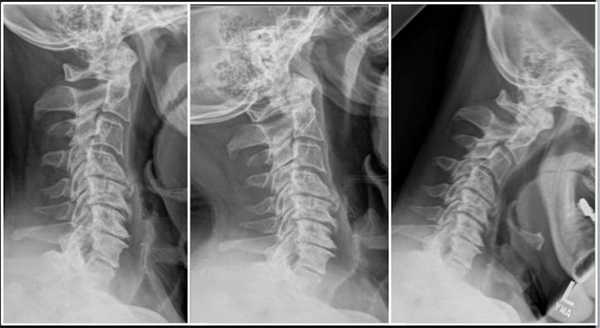

Методы реконструкции тела позвонка

Опухоли различной природы, компрессионные переломы и другие травмы позвоночника, часто получаемые на фоне остеопороза, с каждым годом встречаются все чаще. Ранее они требовали длительного лечения, которое нередко приводило к развитию пневмонии, тромбоза глубоких вен и тромбоэмболии, т. е. тяжелым последствиям, несущим серьезную угрозу для жизни больного. Сегодня медицина может предложить малоинвазивное вмешательство, способное в кратчайшие сроки восстановить структуру поврежденного позвонка при минимальном риске развития осложнения - вертебропластику.

Что такое вертебропластика позвоночника

Вертебропластика представляет собой оперативное вмешательство, в ходе которого для консолидации и упрочнения позвонка применяется костный цемент, который вводят посредством пункционной иглы. Он представляет собой композитный материал на основе полиметилметакрилата (ПММА), отличающийся: